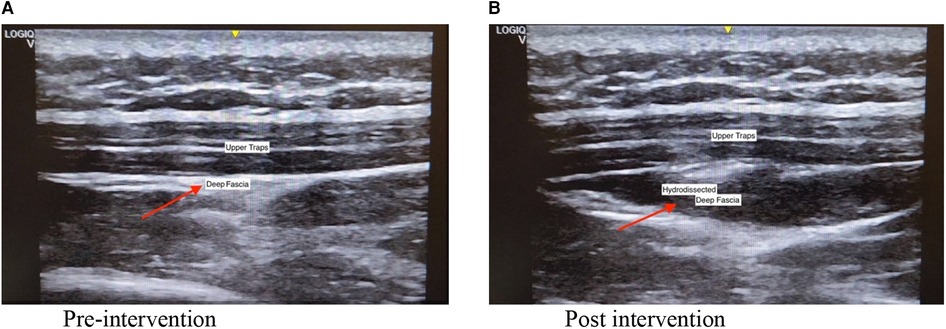

The intervention was performed by a registered musculoskeletal sonologist who has been performing musculoskeletal ultrasounds for more than ten years. Before the intervention, the sonologist palpated the tender nodule to locate the injection site. An ultrasound machine (GE Logic Q) with a linear transducer (5–13 MHz) was used to visualize the fascia during the procedure. Participants were seated with their necks flexed. Topical anesthetic using lidocaine 2% prilocaine 2% (EMLA) cream with transparent film dressing (Tegaderm) on the target site and ice compress was applied for 30 min. Aseptic preparation of the needle insertion site was performed with Propanol Benzalkonium Chloride and sterile drapes. With the use of in plane approach, the sonologist injected the saline anesthetic solution (1 cc 2% lidocaine + 5 cc NSS) between the fascia of the trapezius muscle and the fascia of the muscle directly under it with ultrasound guidance. This was followed by applying direct pressure and dressing over the injection site. Figure 2 shows the pre and post procedure scan of the upper trapezius that underwent hydrodissection.